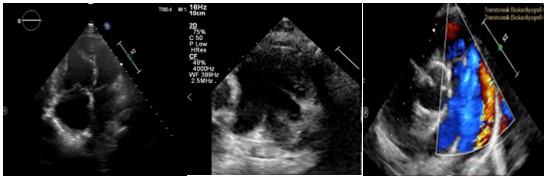

Etyolojiyi tespit etmek, intrakardiyak şantları ve RV fonksiyonlarını değerlendirmek, pulmoner arter basıncını (PAP) belirlemek, eşlik eden ve katkıda bulunan faktörleri saptamak için yapılan transtorasik ekokardiyografisinde; 4 boşluk ve kısa eksen görüntülerde sağ kap boşluklarının geniş olduğu, ventriküler septumun sola şift yaptığı, sistolde daha belirgin olmak üzere D-shaped görünüm olduğu, TAPSE normal sınırlarda olduğu, pulmoner arterin geniş olduğu (30mm) izlendi. Kısa eksen ve suprasternal çalışmalarda geniş bir patent duktus arteriyozus varlığı saptandı, 2 yönlü şant mevcuttu ve  pulmoner arter basıncı sistemik idi (Şekil 1, 2, 3).

Åžekil 1, 2, 3